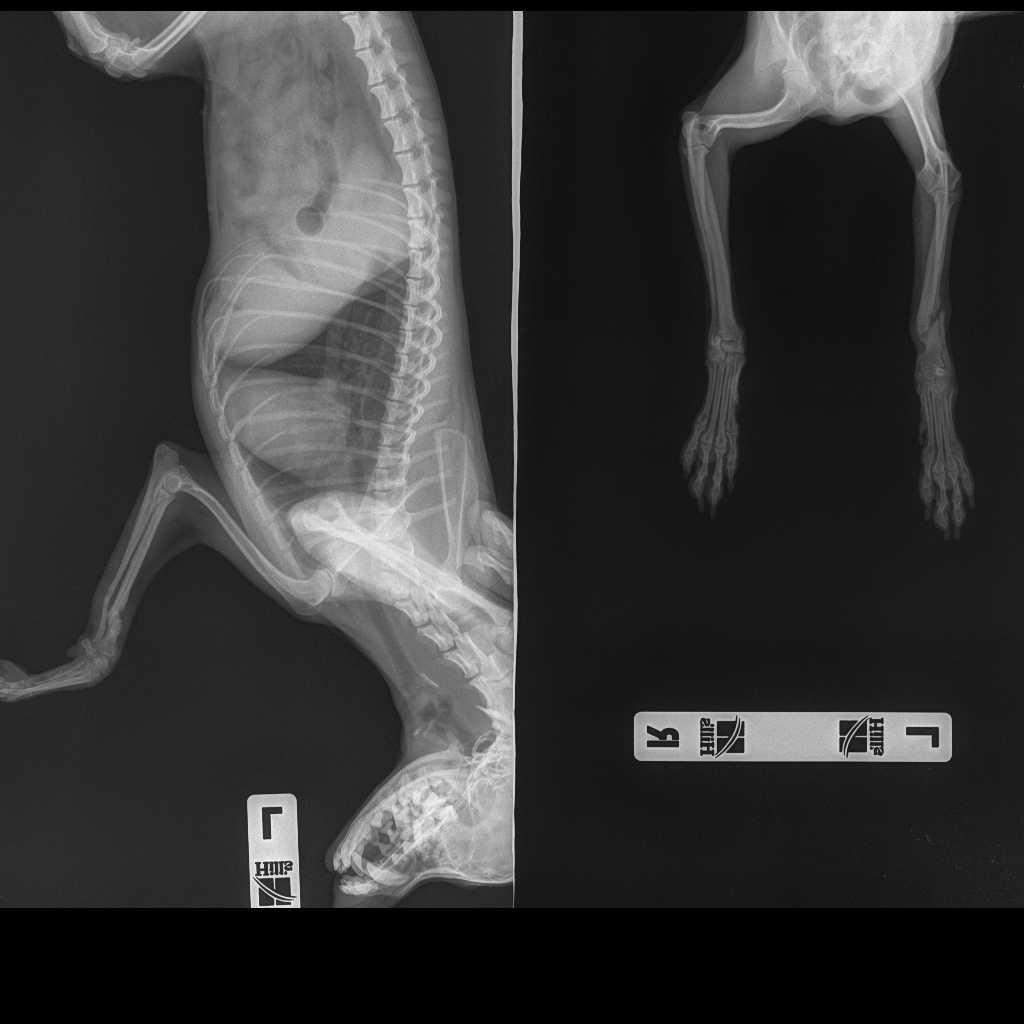

Всем доброго времени суток! ) час назад вернулись домой из Кирова.

Операция прошла успешно, как сказали врачи. Поставили две титановые пластины, 5 шурупов и огроооомный гипс на всю лапку.

Проводили зачистку кости, так как не все хорошо у неё там было.

Теперь несколько дней будем на антибиотиках и три недели в гипсе

Через 2-3 месяца снова рентген и возможно снимут пластину. Снова под наркозом((

До операции сделали рентген. Снимок приложу. Увидев его, я, конечно, расстроилась

Теперь путь только на восстановление. Надеюсь Ася все перенесет легко и пойдёт на поправку. А пока она места себе не находит, плачет иногда. Видимо и болит, и неудобство от гипса испытывает...